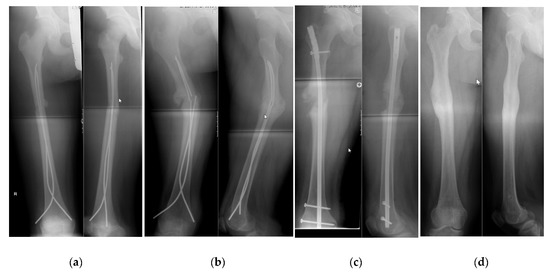

4.2. Demographics, Radiographic Analysis and Complications